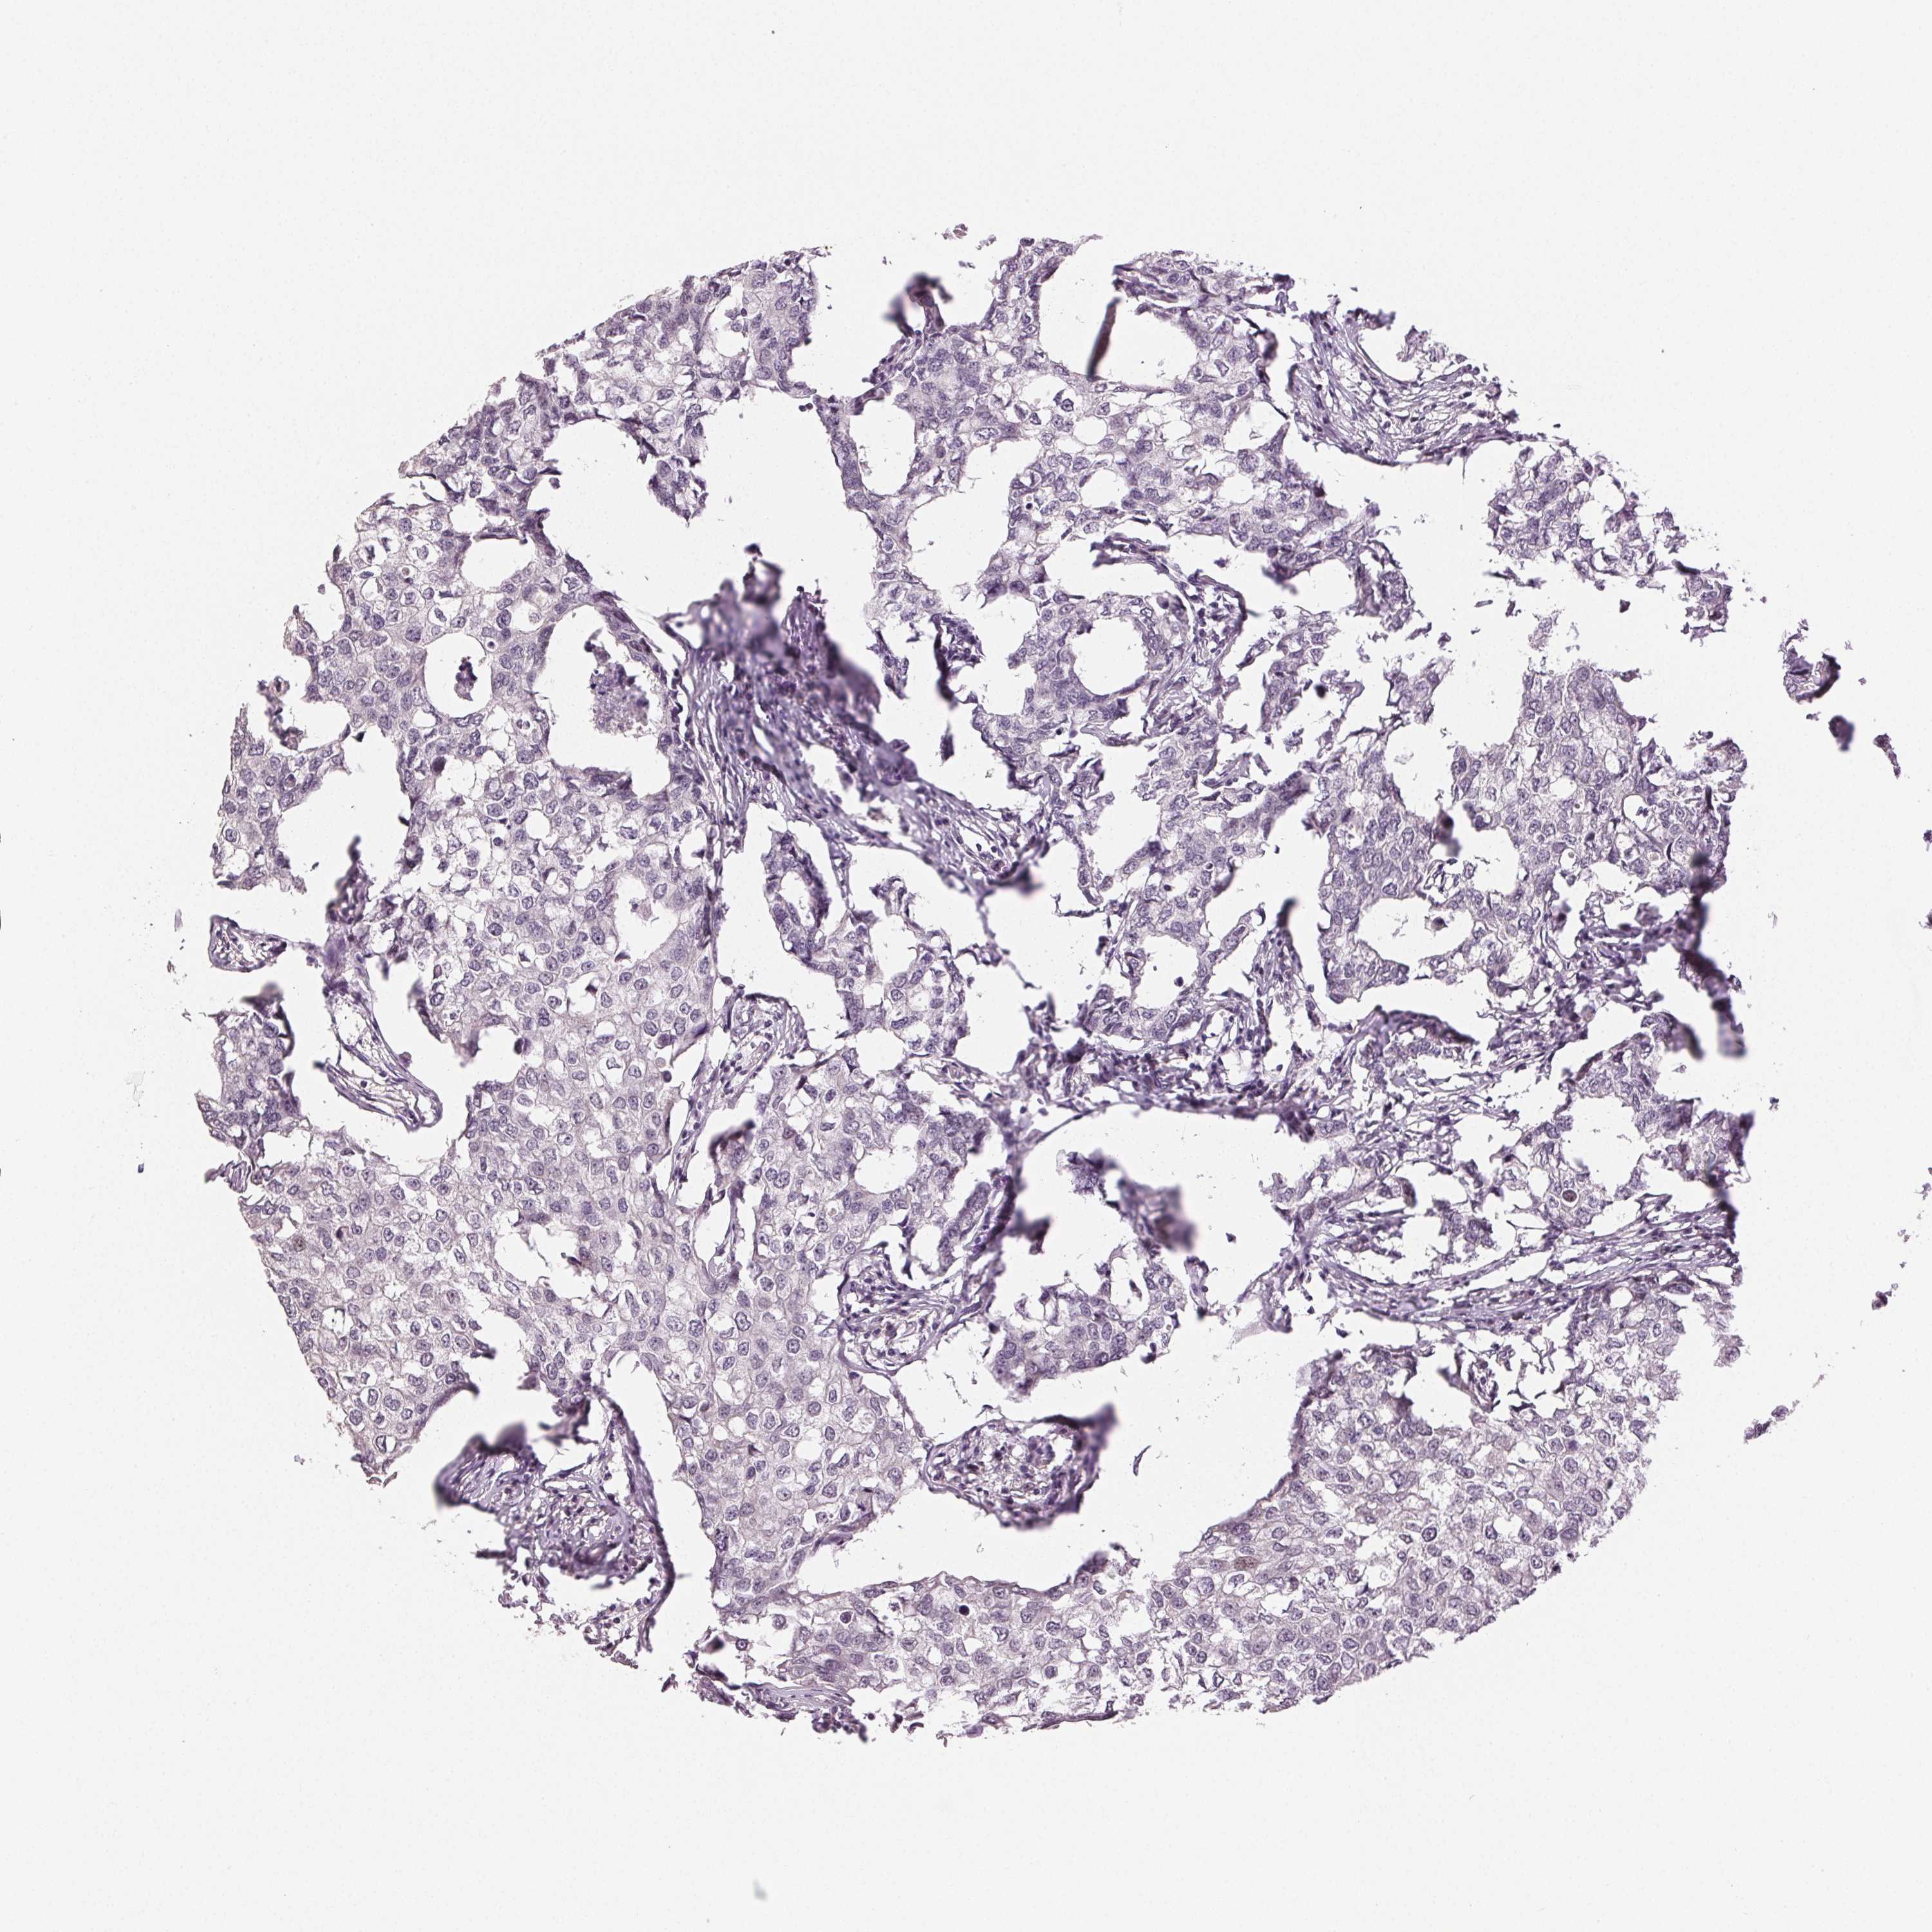

CANCER BREAST CANCER Show tissue menu

BRCA TCGA BRCA VALIDATION PROTEIN EXPRESSION

ANTIBODIES

AND

VALIDATION